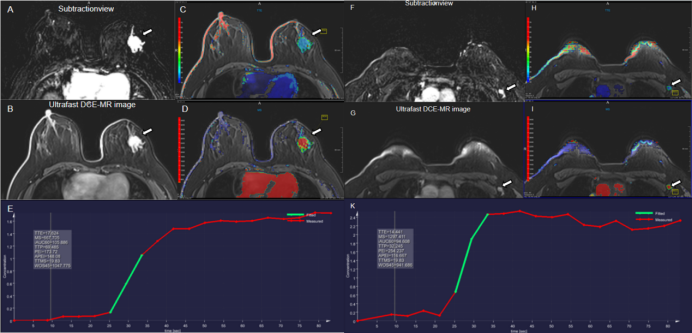

Figure 3. A 61-year-old woman with high-grade ductal carcinoma in the right breast without axillary lymph node metastasis. An irregular heterogeneous enhancing mass and a lymph node in the right breast is shown in the (A, F) early phase MR subtraction images, (B, G), ultrafast DCE images, (C, H) time to enhancement (TTE) maps (C, 22.96s; H, 37.58s), (D, I) maximum slope (MS) maps (D, 4.6%/s; I, 2.8%/s), and (E,K) represent the early time-intensity curves of breast tumor and lymph node, respectively.